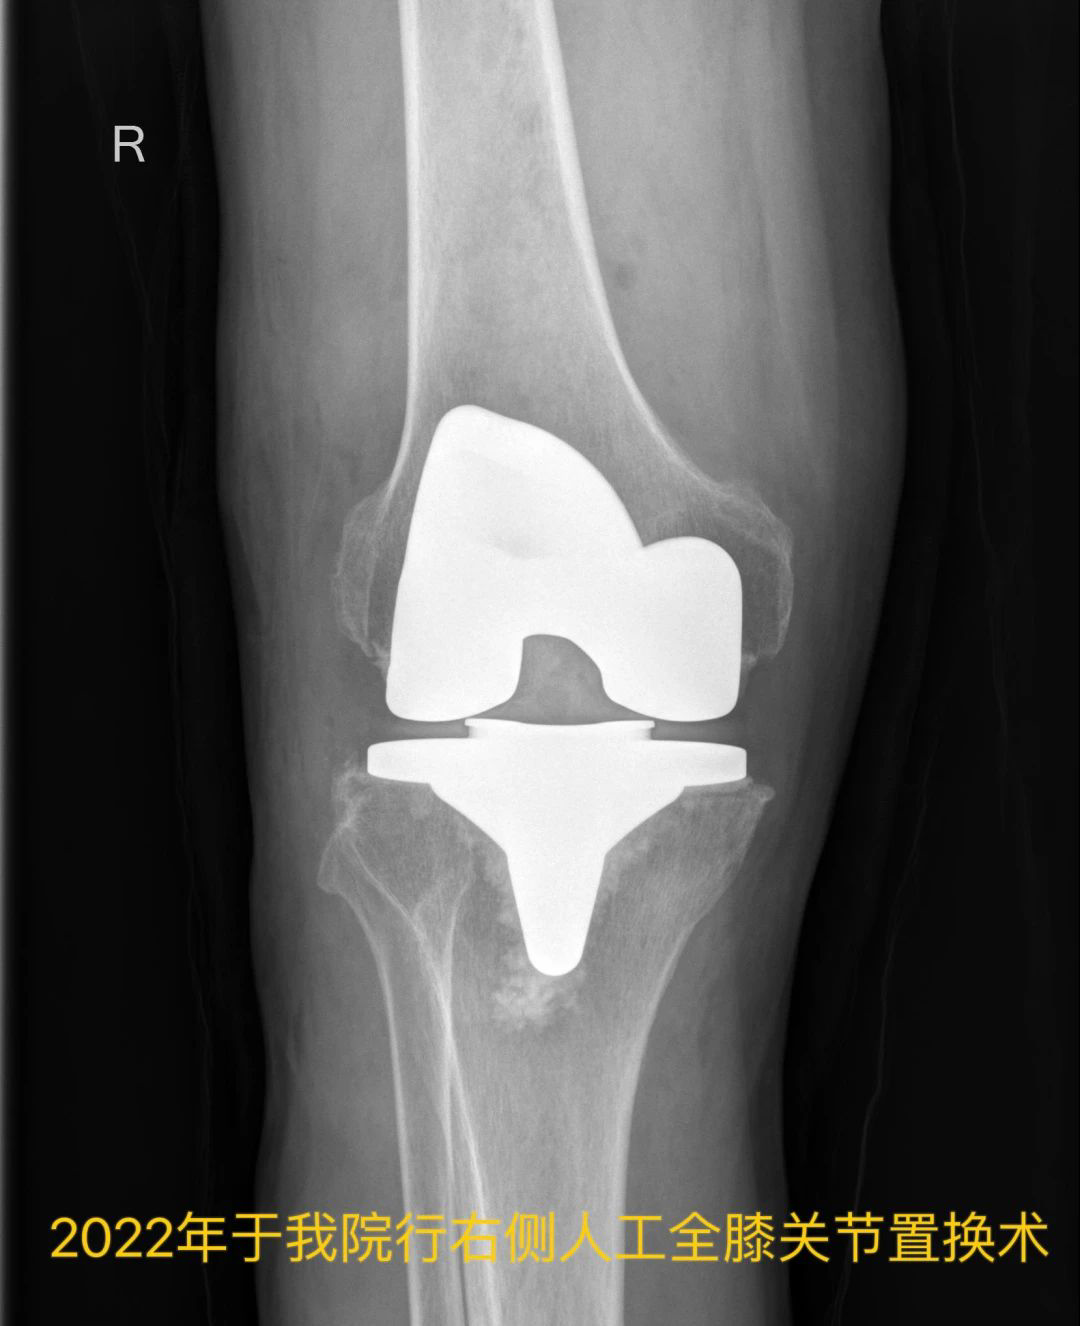

今年64岁的王大爷(化姓),双侧髋、膝关节疼痛十余年,六年前因“腰腿疼痛”于上海长征医院行腰后路减压植骨融合内固定术,同年于上海新华医院内分泌/遗传科行基因检测诊断为“黑尿病”,四年前因“左髋疼痛”于我院行“左侧人工全髋关节置换术”,一年前因“右膝疼痛”于我院行“右侧人工全膝关节置换术”。

王大爷实施了左侧人工全膝关节置换术

复查示左膝关节假体位置良好